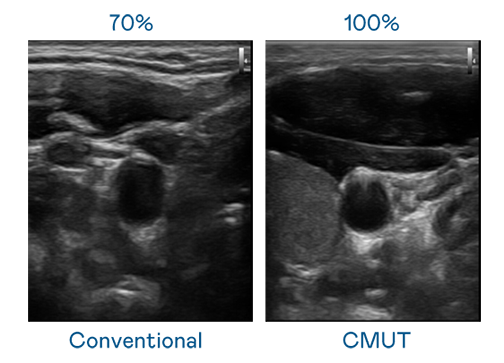

CMUT 技术是一种用电容式微机电元件来产生超音波讯号的技术。与传统 PZT 压电式技术相比,CMUT 频宽增加 30%,更宽频的超音波讯号让影像解析度大幅提升,是实现高影像品质医疗超音波扫描、促进精准医疗发展的关键技术。

超音波影像的解析度高低,首先取决于探头能发出的讯号频宽。恒峰国际 CMUT 可提供高清晰的超音波讯号,提供高频宽、高灵敏度、影像纹理细节更高的超音波影像,协助医护人员缩短影像判读时间及利用精准的医疗影像进行诊断。